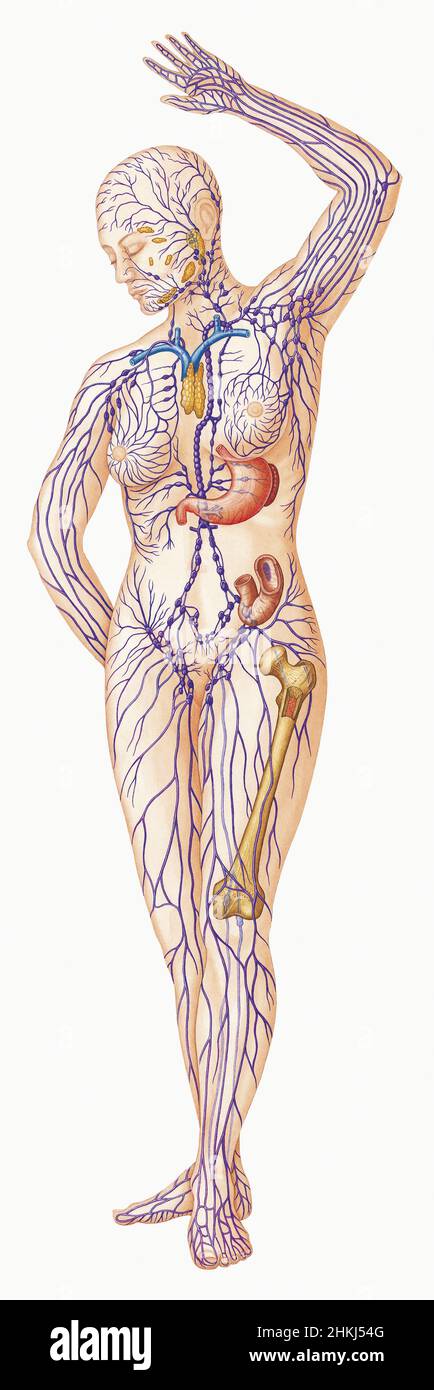

Изображения и схемы: как выглядит лимфа